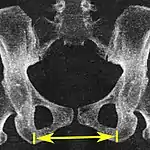

Intertuberous diameter, as a measure of the transverse measure of the pelvic outlet